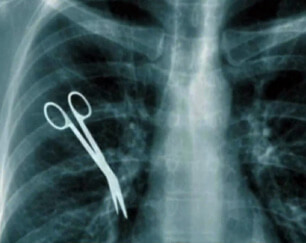

Our mediation documentary videos are powerful tools for addressing opposing parties' liability and providing a comprehensive explanation of the plaintiff's damages. By incorporating on-camera interviews with expert witnesses, including forensic engineers, we can effectively demonstrate the full extent of the opposing counsel's client's exposure. Additionally, the insights shared by treating physicians and life planning experts through on-camera interviews offer invaluable support for the plaintiff's demand.